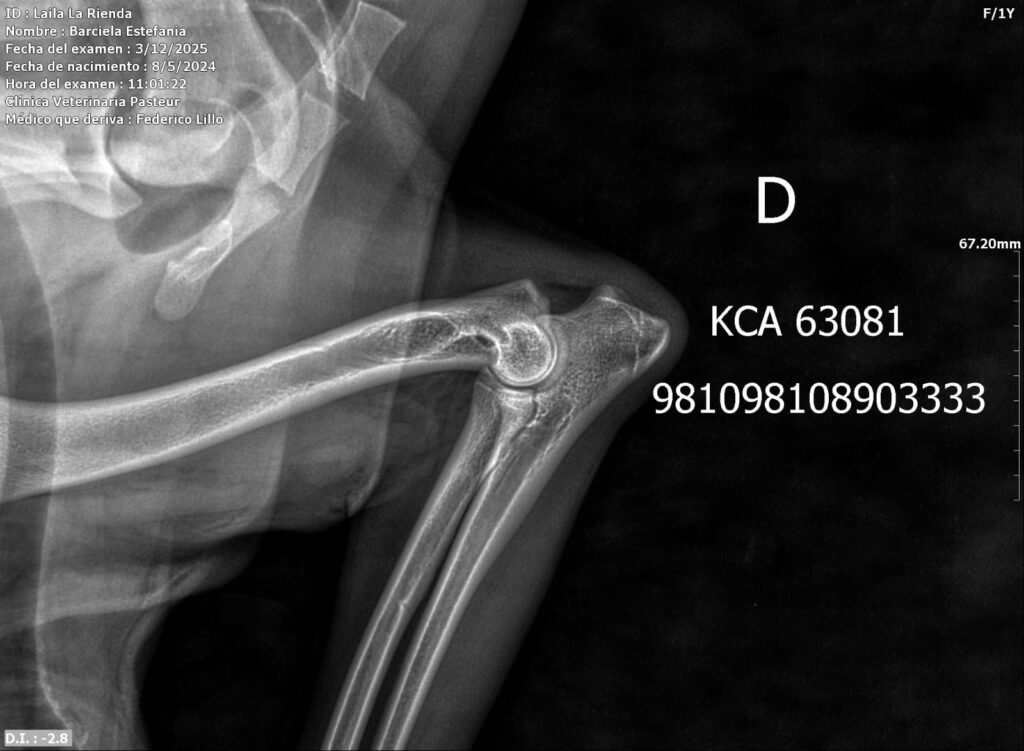

Placas de caderas y codos en La Rienda Border Collie

Realizamos radiografías oficiales de caderas y codos a nuestros reproductores, evaluadas por profesionales veterinarios especializados.

Estos estudios permiten detectar posibles patologías hereditarias, como la displasia de cadera y de codo, ayudando a reducir su incidencia generación tras generación.

✔ Clasificación A en caderas y codos, indicativo de articulaciones sanas y excelente conformación

✔ Clasificación A en codos y B en caderas, siempre informada con total transparencia y criterio de selección responsable